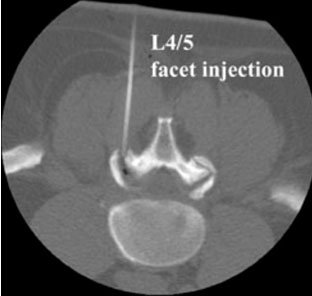

Facet joint block is an injection of local anaesthetic and steroid that reduces inflammation in facet joint space of vertebrae of spine and relieves back pain. It is a minimally invasive procedure and we do it under CT guidance. Facet joints are made of cartilage and are responsible for your flexibility and ability to bend and twist. Your nerves pass through them to go to other parts of your body.The vertebrae in spine have two